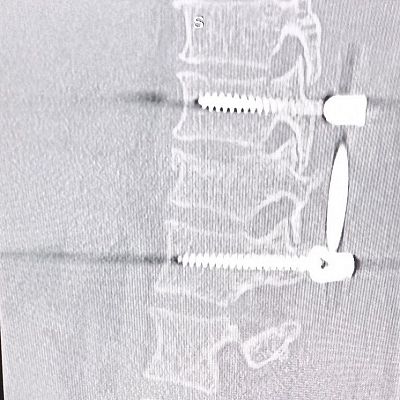

Когда мужчина стал ремонтировать свое авто, он не предполагал, что дело закончится больничной койкой. Детали, естественно, не уточним, но он без помощи домкрата решил поднять машину и… На снимке, сделанном в приемном отделении Московской областной больницы имени профессора Розанова В.Н., куда его привезли практически обездвиженного, перелом 11 грудного позвонка.

«Во время операции провели транспедикулярную фиксацию позвоночника», - рассказывает заведующая нейрохирургическим отделением Московской областной больницы имени профессора Розанова В.Н. Нина Николаевна Вознесенская https://t.me/voznesenskai_neirohirurg - Основы этой операции были разработаны в середине XX столетия - на тот момент конструкции выполнялись из нержавеющей стали. Но когда появились аппараты МРТ (магнитно-резонансной томографии), это стало огромной проблемой: с одной стороны, магнитно-резонансная томография стала одним из важнейших исследований позвоночника, а с другой - стальные фиксаторы не позволяли его проводить. Так появились титановые сплавы, которые сейчас используются».

Металлоконструкцию, которой зафиксирован позвоночник, пациент не будет чувствовать. Этот легкий титановый сплав не будет мешать движениям и не будет заметен рамкам металлоискателей. Так что при входе в официальные учреждения, метро, аэропорты и т.д. мужчине не придется носить с собой справку о том, что он был прооперирован. Эта конструкция будет видна лишь на рентгеновских снимках, на компьютерной и магнитно-резонансной томографии - ее установка не является противопоказанием для этих обследований.